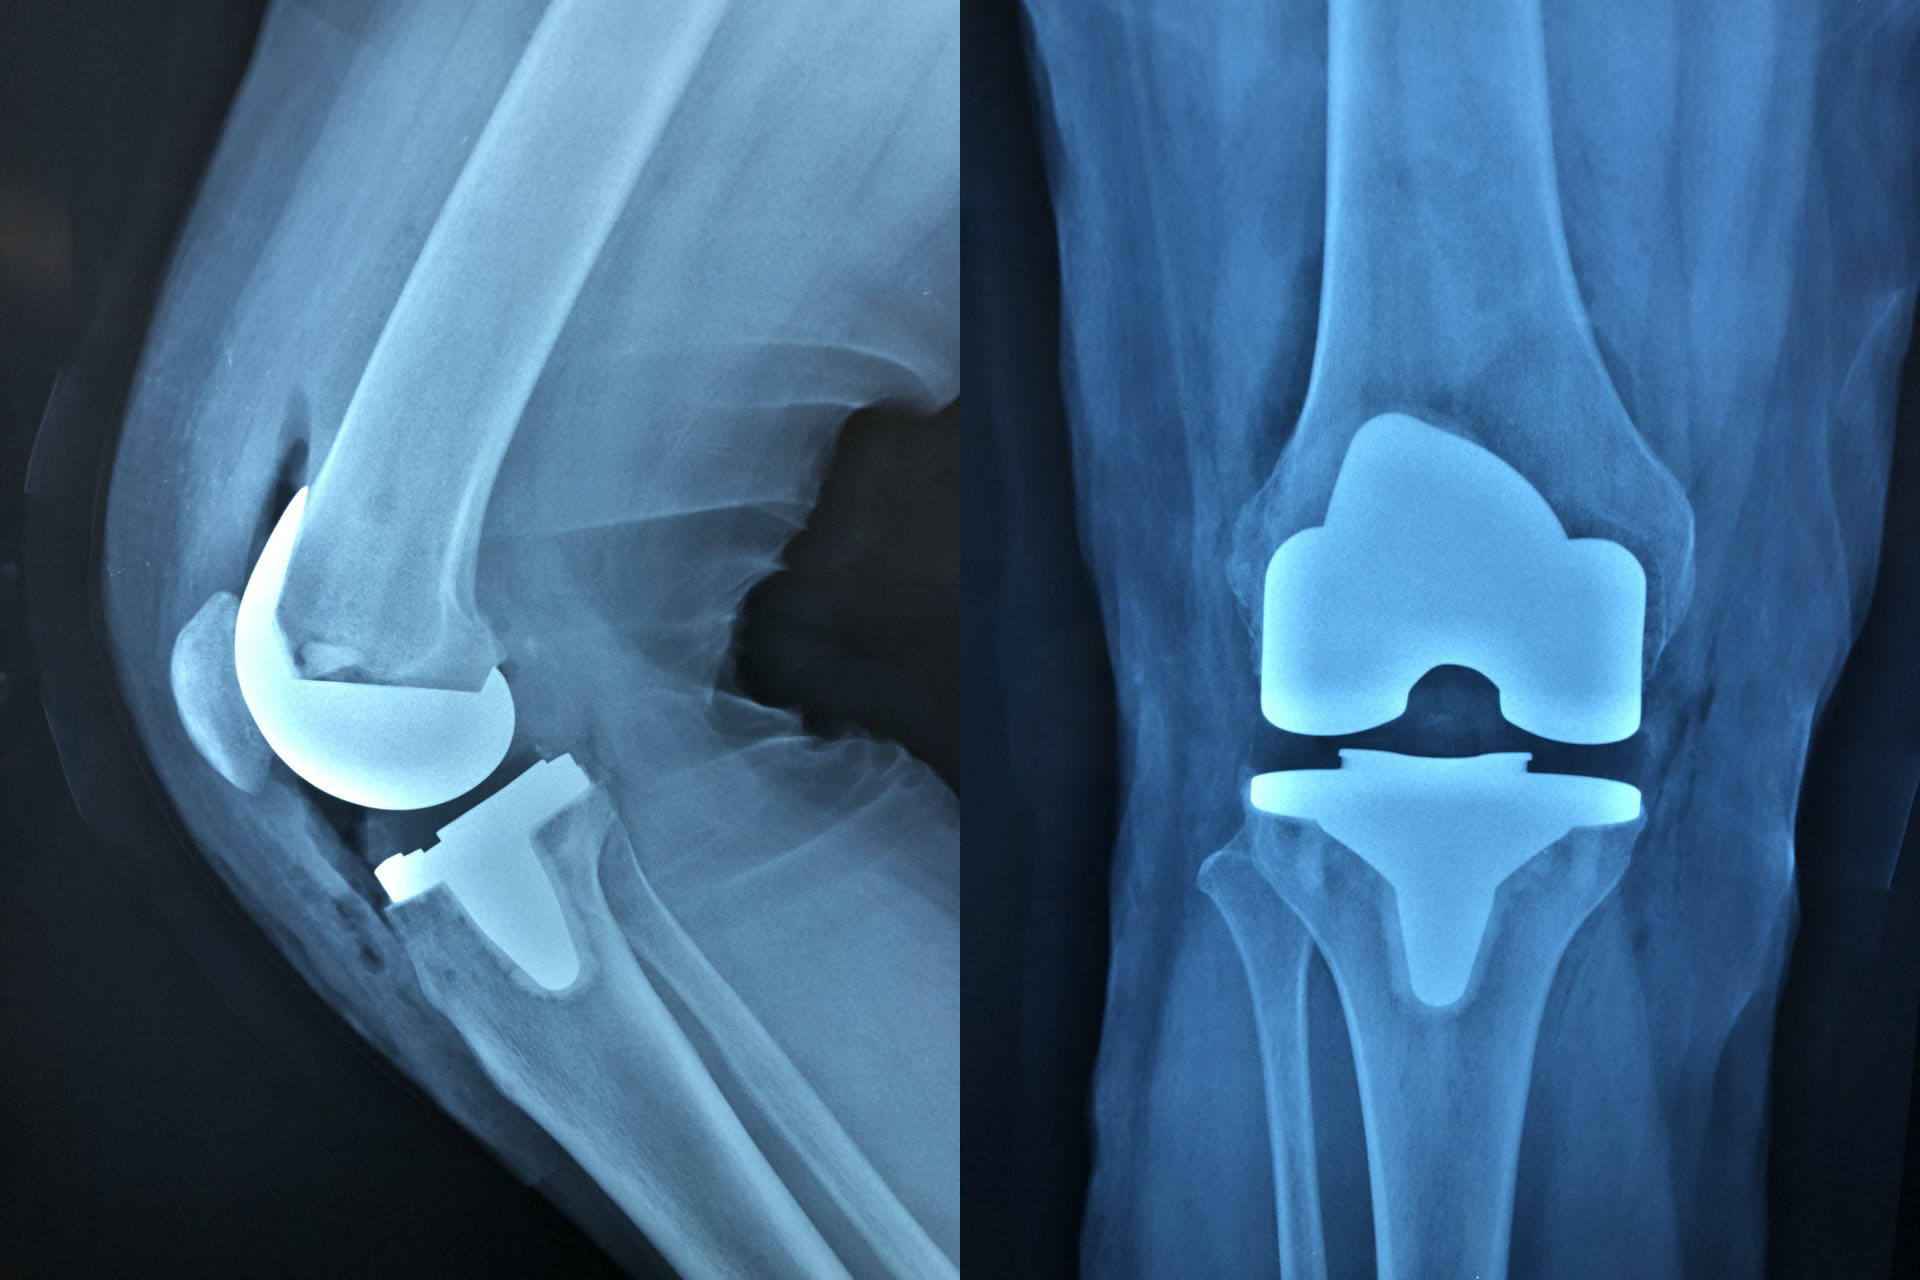

Prótesis de Rodilla

La cirugía de reconstrucción articular es la última opción en el tratamiento en la fase de mayor desgaste del cartílago en la que el dolor es una constante al igual que la limitación de la movilidad de la rodilla.

La tecnología robótica Mako representa un gran avance en la cirugía de prótesis de rodilla. Al proporcionar a los cirujanos información preoperatoria detallada y asistencia durante la cirugía, se logra una mayor precisión en la colocación de la prótesis y en los cortes realizados, lo que se traduce en una mejor calidad de vida para los pacientes y una recuperación más efectiva.